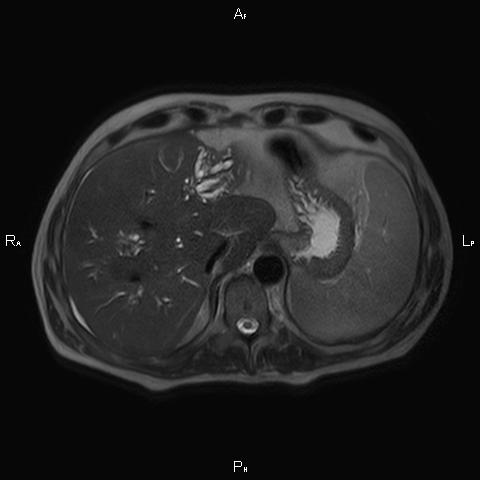

ΚΛΙΝΙΚΑ ΣΤΟΙΧΕΙΑ – ΙΣΤΟΡΙΚΟ

Ανώδυνος ίκτερος και παθολογικά ηπατικά ένζυμα. Ιστορικό πιθανής σκληρυντικής χολαγγειίτιδας

ΑΠΕΙΚΟΝΙΣΤΙΚΟΣ ΕΛΕΓΧΟΣ

Μαγνητική τομογραφία.

Οι αρχικές εξετάσεις εκλογής, όσον αφορά τον απεικονιστικό κυρίως έλεγχο, σε ασθενή προσερχόμενο στο Νοσοκομείο με αποφρακτικό ίκτερο, είναι το υπερηχογράφημα και η αξονική τομογραφία. Οι εξετάσεις αυτές έχουν αποδειχθεί ικανές να προσδώσουν έμμεσα και άμεσα στοιχεία για τη διάγνωση του χολαγγειοκαρκινώματος, όμως κυρίαρχη εξέταση για την διάγνωση του χολαγγειοκαρκινώματος είναι η μαγνητική τομογραφία (MRI, MRCP, MRA).